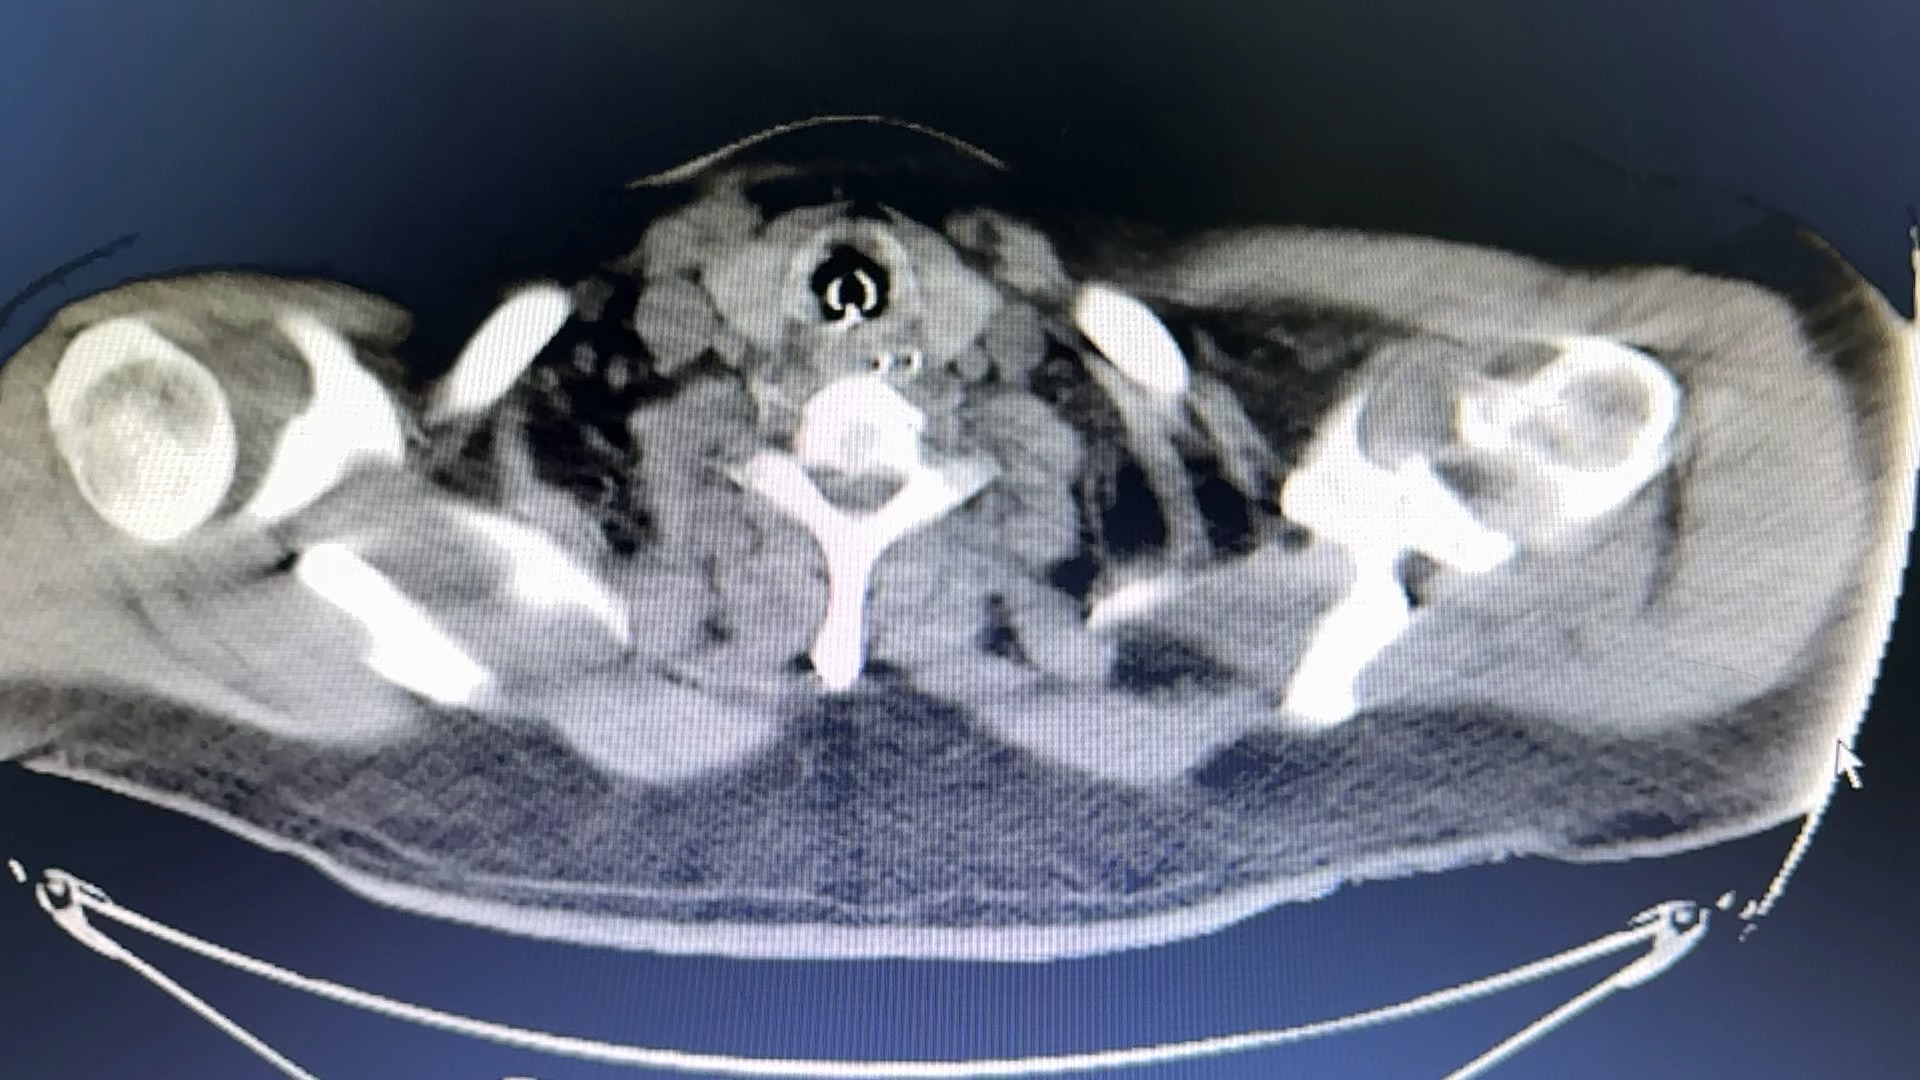

带出去复查了一个CT如下:

CT比第一次稍好转!